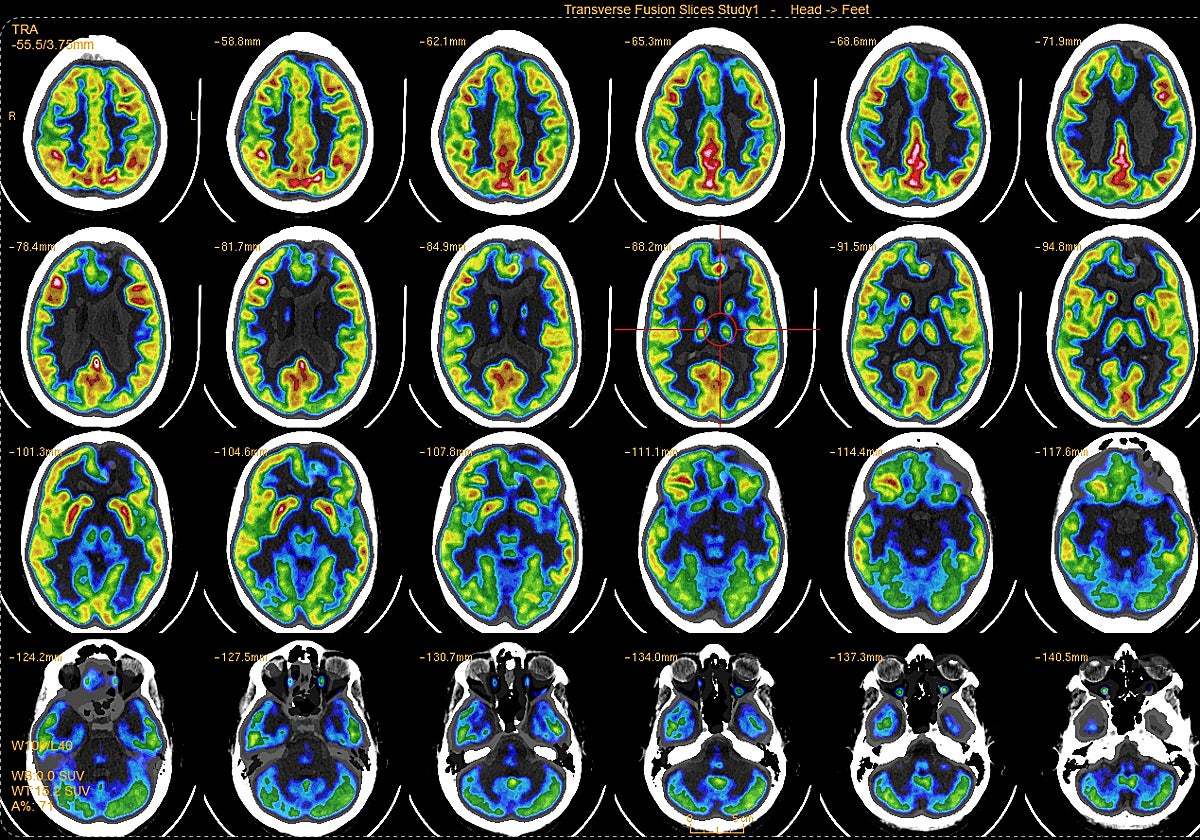

El equipo investigador estudió a cuatro pacientes que fallecieron debido a un paro cardíaco en el hospital mientras estaban monitorizados con un electroencefalograma. Los cuatro pacientes estaban en coma y no respondían. Finalmente, se determinó que estaban más allá de la ayuda médica y, con el permiso de sus familias, se les retiró el soporte vital que les mantenía con vida.

Oleada de ondas gamma

Al retirar el ventilador, dos de los pacientes mostraron un aumento en la frecuencia cardíaca junto con una oleada de actividad de ondas gamma, considerada la actividad cerebral más rápida y asociada con la conciencia.

Además, esa actividad se detectó en la llamada 'zona caliente' de la conciencia en el cerebro, la unión entre los lóbulos temporal, parietal y occipital en la parte posterior del cerebro. Esta zona se relaciona con los sueños, las alucinaciones visuales que se registran en una crisis de epilepsia y los estados alterados de conciencia en otros estudios del cerebro.

Los dos pacientes tenían informes previos de convulsiones, pero no tuvieron ninguna crisis durante la hora anterior a su muerte, explica la neuróloga Nusha Mihaylova que desde 2015 recopila los datos de pacientes fallecidos en la UCI. Los otros dos pacientes no mostraron el mismo aumento en la frecuencia cardíaca al retirarlos del soporte vital ni tuvieron una mayor actividad cerebral.